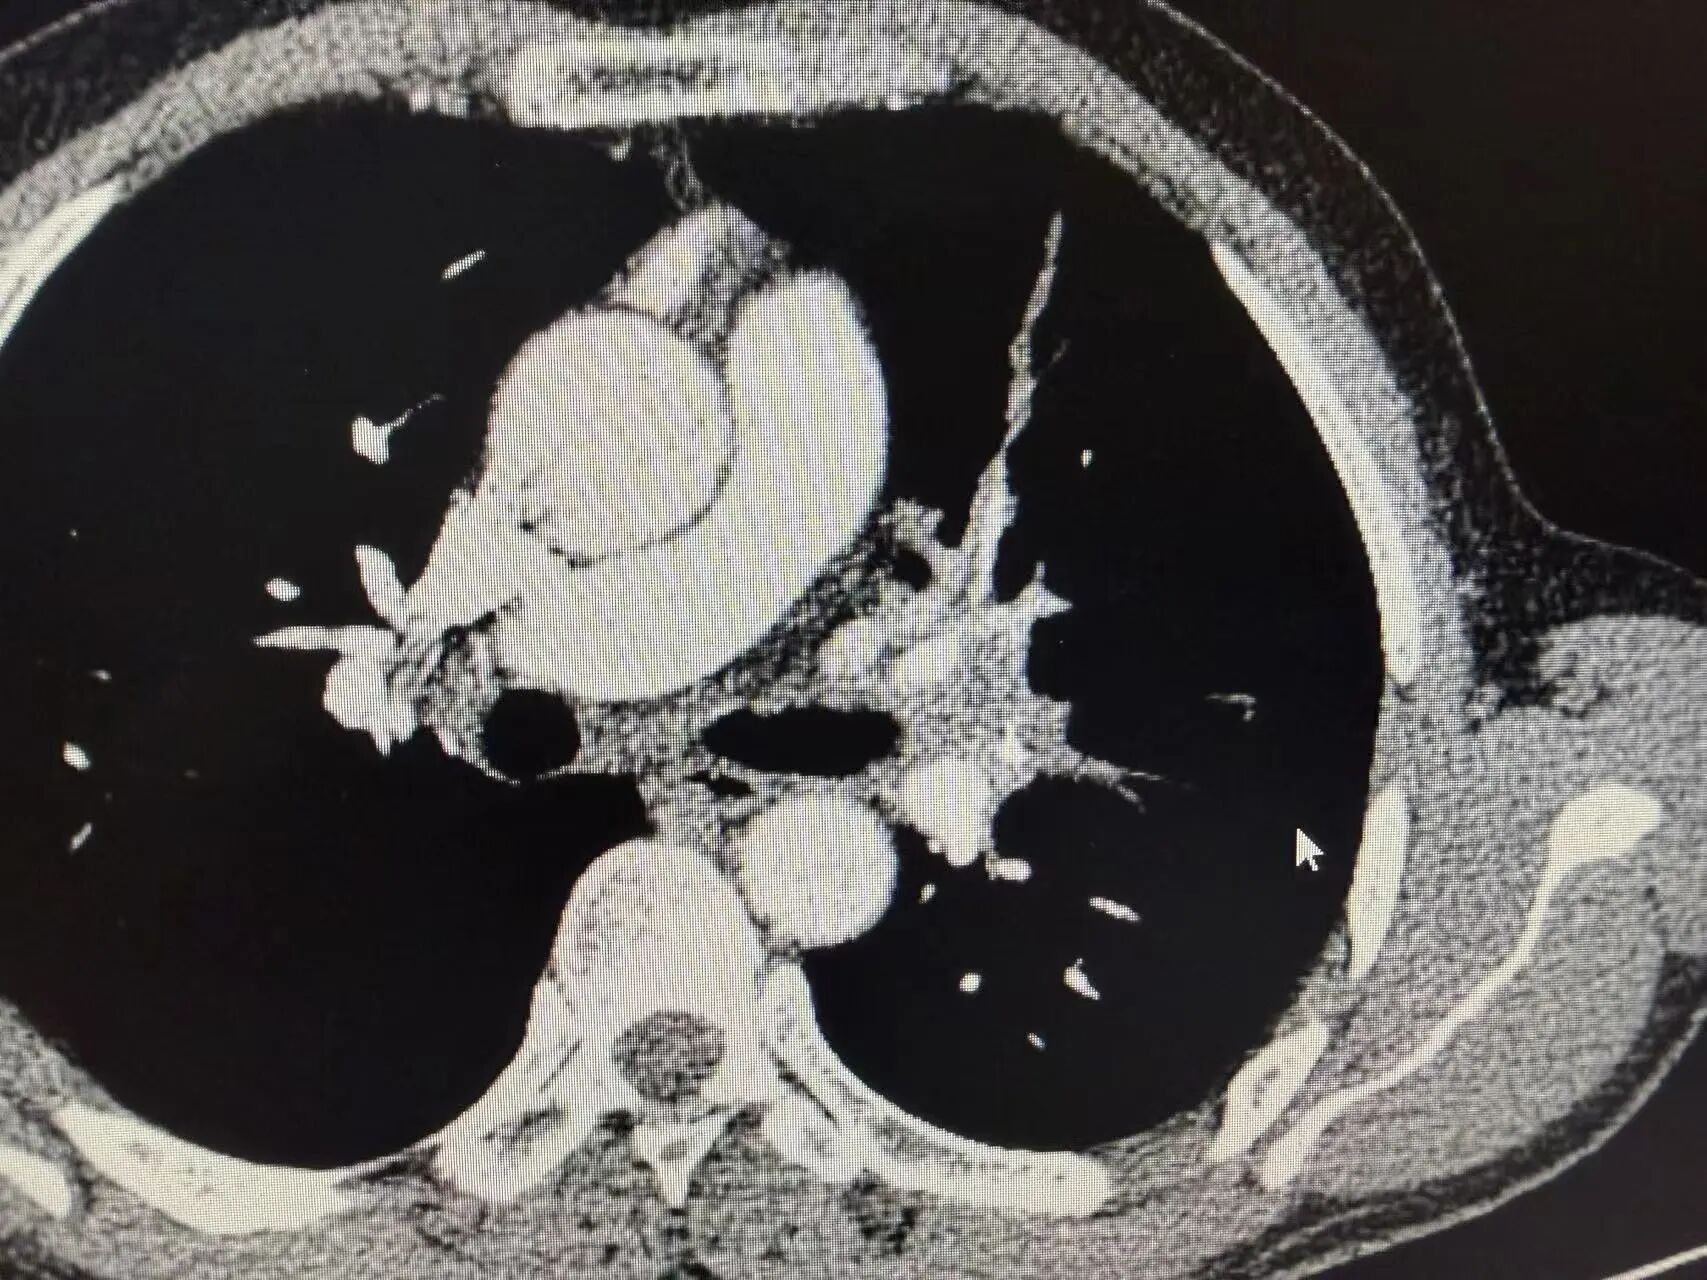

新辅助治疗前CT:可见左上肺中央型占位,肿瘤侵犯血管

1-4.jpg

1-5.jpg

新辅助治疗后CT:肿瘤明显缩小